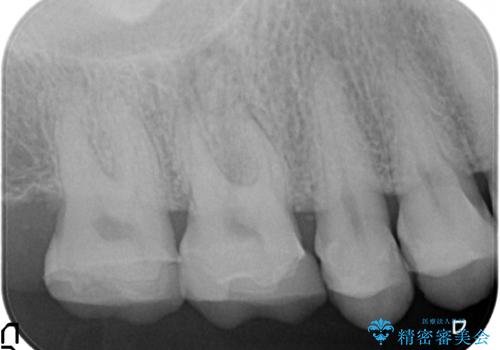

- 他院にて右上6の神経が死んでいるため根管治療が必要だと言われ当院にいらっしゃった方の症例です。

X線上で根尖病変を認めたため根管治療を行い、その後オールセラミッククラウンによる補綴を行いました